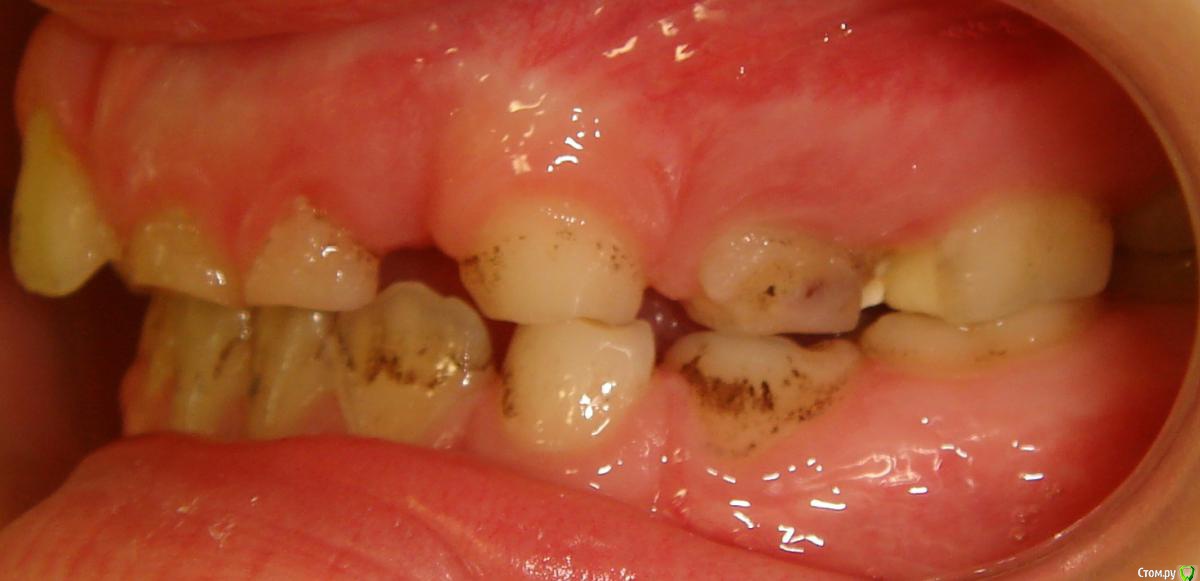

Opdihatop Опубликовано 9 января, 2017 Поделиться Опубликовано 9 января, 2017 Здравствуйте, коллеги! Хотел бы узнать ваше мнение по пациентке. Девочке 7 лет. План лечения в общем мне ясен и понятен. Меня интересует вопрос, когда лучше в данном случае убирать сверхкомплектный премоляр в области 21 зуба, потому что он начал двигать ц.л. вправо. Заранее спасибо! Ссылка на комментарий

Dok22 Опубликовано 11 января, 2017 Поделиться Опубликовано 11 января, 2017 Это не премоляр просто так виден 2-х мерный срез нужно КТ его грамотная интерпретация и хороший хирург.Сверхкомплектный удалять надо он блокирует 21 и 22. Ссылка на комментарий

Давлетшин Опубликовано 12 января, 2017 Поделиться Опубликовано 12 января, 2017 (изменено) С позиции детского амбулаторного хирурга-стоматолога я не трогал бы до окончания формирования корней, а 61, 62 убрал бы. Просто не лез, и не лезу. Да возможно есть есть очень хорошие хирурги с седацией и т.п. пусть они (он, она) решает. Из личного опыта у ребенка сверхкомплектный мешал прорезыванию 21 в семь лет, я все обьяснил сказал:" давайте ждать". Родители понимающе сказали:" давайте", и пошли снова к ортодонту, та в свою очередь отправила к своему "крутому" хирургу. Соответственно сверхкомплектный был удален (сверхкомлектный не прорезался) а у 21 сформирована была только коронка. Через три года, в 10 лет пришли снова, и у меня спрашивают:" где зуб"? Я направил на R-грамму, где увидел что коронка 21 "плавает" в очаге разряжения костной ткани размером 1.5*1.5 см. слизистая была в норме. Об"яснил, рассказал, показал риски для 11 и 22 зуба. и не сформированный 21 был удален. Причем после разреза слизистой и надкостницы с небной стороны сам выпал из полости "кисты". Не знаю где были ошибки. может мне надо было проявить эмоции и внушить что не надо удалять. Не знаю каков был ход операции, задели не задели ростковую зону 21 зуба, нарушили что нибудь не нарушили. Факт что ребенок остался без переднего зуба. Хорошо, мне хватило ума не лезть туда. Может ошибка родителей что не успокоились, и начали панику проявлять. Хирурга в той частной уже не было, наверно импланты крутит. Причем в разделе детская стоматология - есть мой фотоотчет по одонтоме. Т е если нет рисков повредить зачаток (зону роста корня)я лезу. Надо взвесить риски, сейчас что то делать, или же в 10-12 лет вытаскивать 21,22 зубы после формирования корней. Хорошо будет если срезы КТ добавите трансверсали. Даст Бог доучусь в орде на ортодонта, и начав работать ортодонтом думаю не изменю мнения при этом случае, зная работу детского хирурга. Снимков, КТ предоставить не могу потому, что шороха много было, оформления, переписывания карточки много было. Естественно когда я консультировал я все на словах говорил, через три года и не вспомнить. Ортодонт ни при чем, я типа не отправляла, они сами. Они кричали что именно ортодонт именно к определенному хирургу отправила, хирурга там уже давно и нет, и контора поменяла название. Кароч заведующая карточку под три замка в сейф свой убрала.Извините если много букв. Изменено 12 января, 2017 пользователем Давлетшин 1 Ссылка на комментарий

Dok22 Опубликовано 12 января, 2017 Поделиться Опубликовано 12 января, 2017 С одной стороны вы правы риск повредить 21 22 есть,но если сверхкомплектный 21 сформируется полностью все будет сложнее сейчас при наличии грамотного КТ и хирурга зачаток сверхкомплектного 21 убрать проще.Убирал подобное в 6 и 9 лет в 9 сложнее. Попробую найти КТ выложить. Ссылка на комментарий

Yana guapa Опубликовано 13 января, 2017 Поделиться Опубликовано 13 января, 2017 убрать молочный ц. резец. подождать 6-8 месяцев хотя бы (лучше год) - все ростковые зоны уже значительно выше будут, хирург не задет уже.сделать КТ. и удалить сверхкомплектный. Дать возможность опуститься ц. резцу.сильно долго ждать (до полного формирования корней) не вижу смысла. Очень похожа ситуация была у моей девочки (такое же расположение). - очень долго не хотел ц. резец спускаться. Райц-терапия в помощь)) вышел)) Ссылка на комментарий